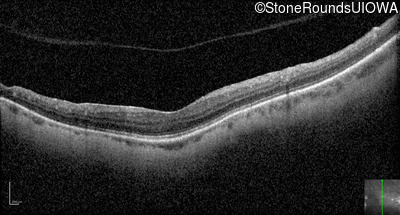

Optical Coherence Tomography - Right - 20/100 +1

Exemplar / OCT Stack

OCT Stack